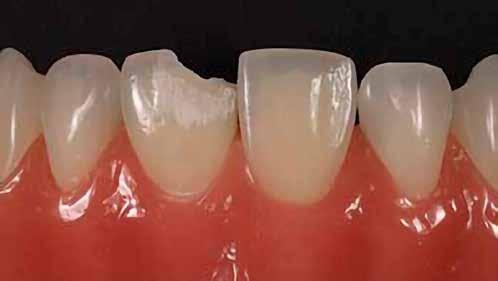

14. ábra: Egy moláris fog preoperatív állapota.

15. ábra: Egy moláris fog postoperatív fotója.